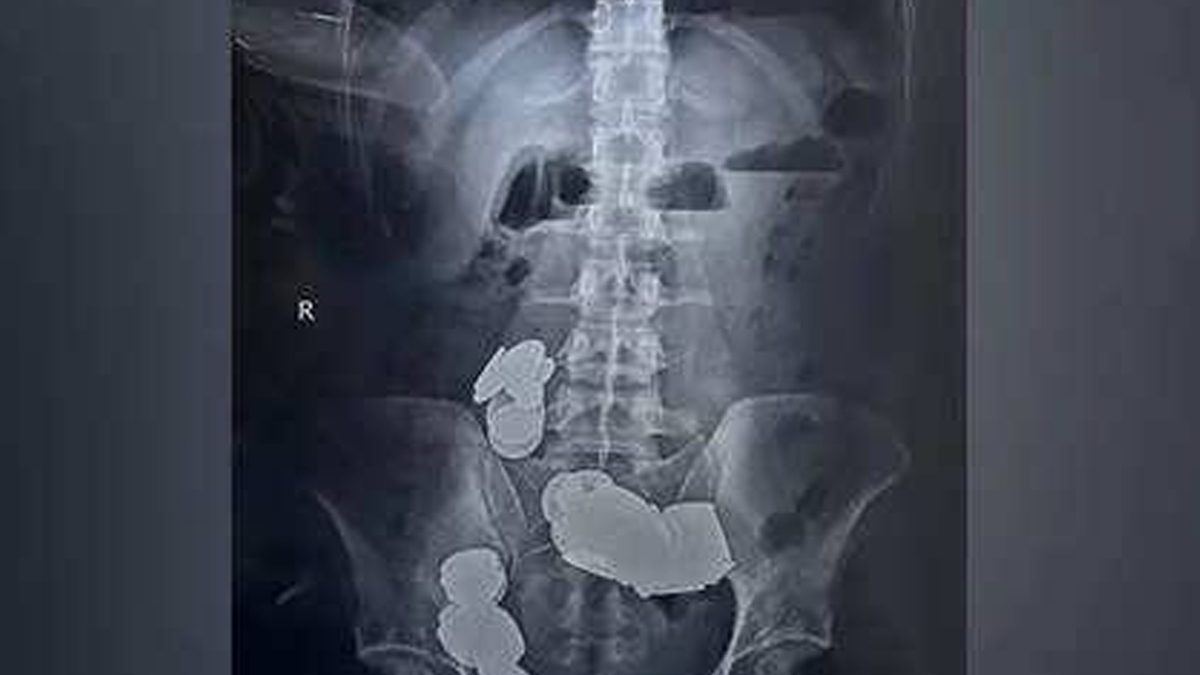

In a bizarre affair, a 26 year old man living in Delhi found a creative way to fulfill his body's requirement of dietary zinc. Reportedly, he was told that consuming a zinc rich diet helps in body building. His solution? Swallow 39 coins and 37 magnets.

The incident became famous after the boy visited Sri Ganga Ram Hospital's emergency ward, complaining about unstoppable vomiting, inability to eat anything and abdominal pain, all of which has been troubling him since the last 20 days.

The coins and magnets had blocked his intestine and stomach, calling for immediate surgical intervention. During the surgery, the doctors discovered that the magnets' attraction had started to pull other objects in his body, causing the intestinal wall to erode and form two separate loops. Fortunately, he is back to normal now after a week long stay at the hospital, equipped with a repaired intestine and the sense that magnets and coins are not to be eaten. If you too have some similar ideas, let me tell you that there are much better and healthier options to have a zinc rich diet.